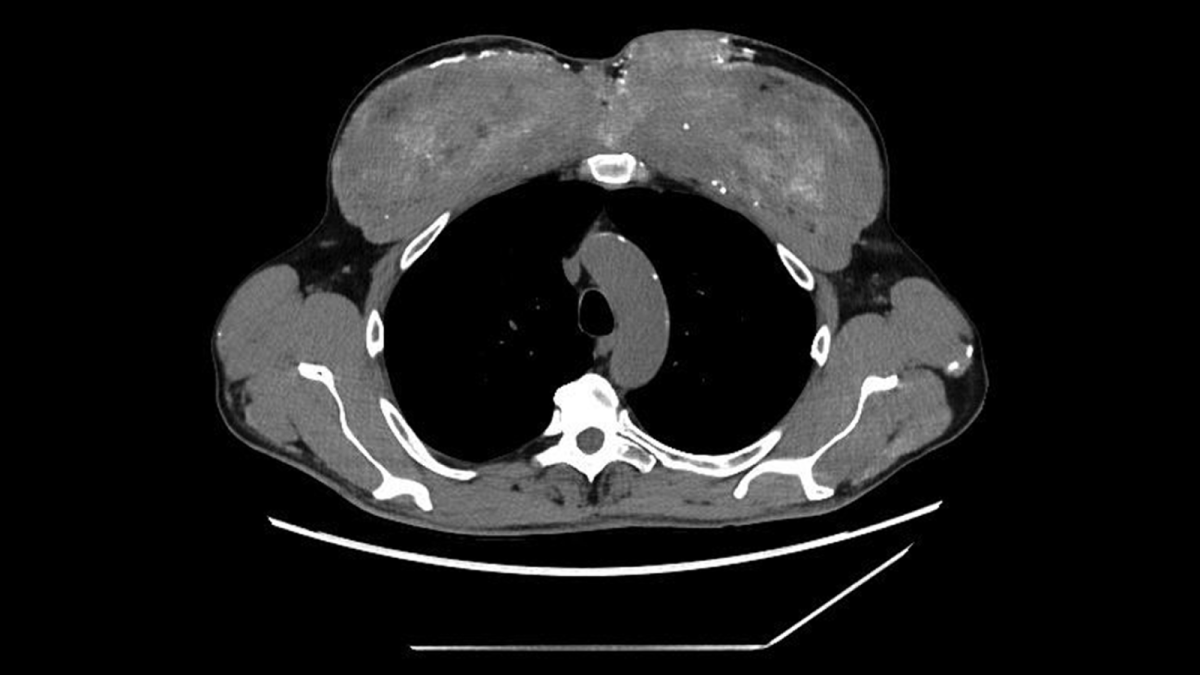

الفحوصات الإضافية

قرر الفريق الطبي إجراء فحوصات تصوير مقطعي، ليتضح أن التكلّسات لا تقتصر على الدم فقط؛ فقد كانت منتشرة في الكليتين والبنكرياس والمعدة، كما ظهرت بقع تشبه الندبات في الرئتين، غير أن أكثر ما أثار الريبة كان التغيّر الغريب في عضلات الصدر، التي بدت متكلّسة بشكل كثيف وغير طبيعي.